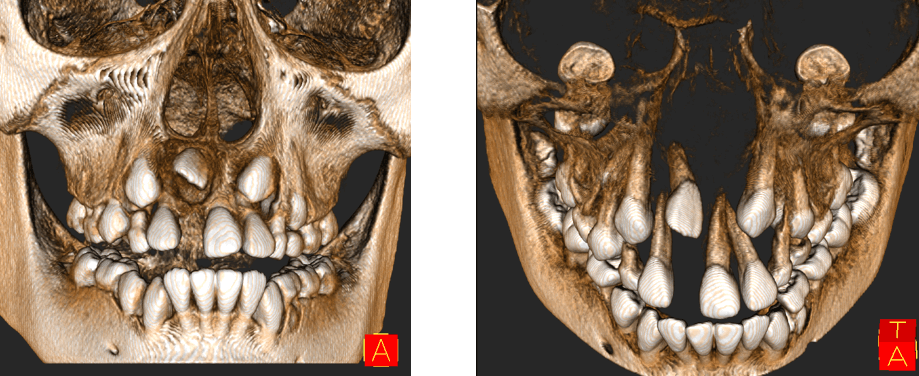

Para diagnóstico radiológico se utiliza CBCT bimaxilar FOV 10 x 8 realizada previo a la colocación de aparatología fija, en donde se observa al diente 1.1 retenido en el piso de fosas nasales en posición horizontal con su saco pericoronario desprovisto de recubrimiento óseo en el borde incisal. (Fig 5)

Fig 5. Cortes en ventana MPR y renderizado 3D

El ápice del diente 1.1 está ubicado en el centro del paladar duro en sentido sagital por lo que el riesgo de necrosis pulpar posterior a la tracción ortodóntica es una complicación a tomar en cuenta en el presente caso. (Fig 6)

Fig 6. Reconstrucción PANOREX y cortes sagitales

La paciente se encuentra en etapa de recambio dentario, se observan los dientes 1.3 y 2.3 en etapa de evolución intraósea, dientes deciduos 5.3 y 6.3 con la reabsorción fisiológica simétrica propia de la edad. Se confirma que la edad cronológica de la paciente coincide con la etapa eruptiva de la misma. (Fig 7 y 8)

Fig 7. Renderizado 3D frontal - Fig 8. Renderizado 3D vista superior